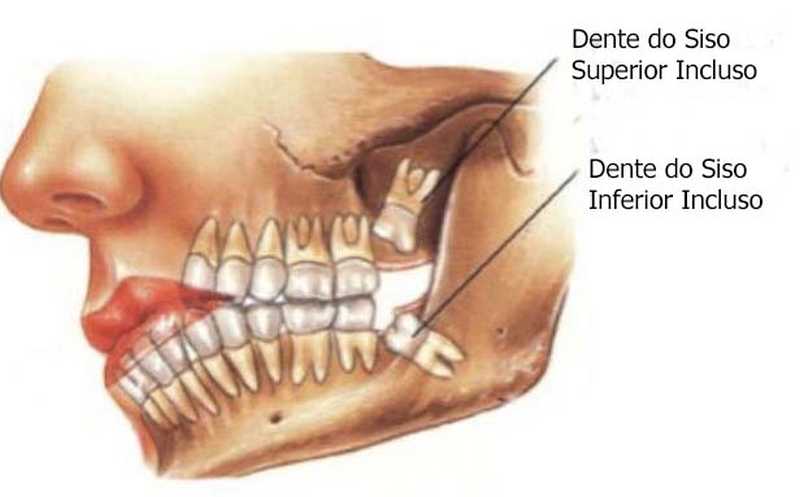

Inicio Especialidades Cirurgia